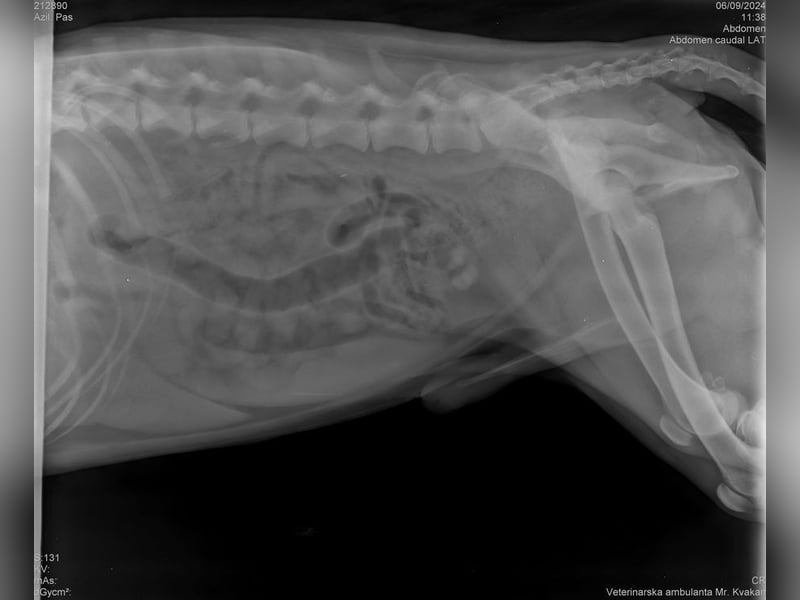

Wir durften ihn deshalb ohne Probleme mit ins Tierheim nehmen, da Yondu Probleme mit der Hüfte und ein etwas kürzeres Beinchen hat. Youdu hat bei einen Besuch beim Tierarzt entsprechende Röntgenbilder von Hüfte und Hinterbeinchen, die den Interessierten in der Bildergalerie zur Verfügung gestellt werden.